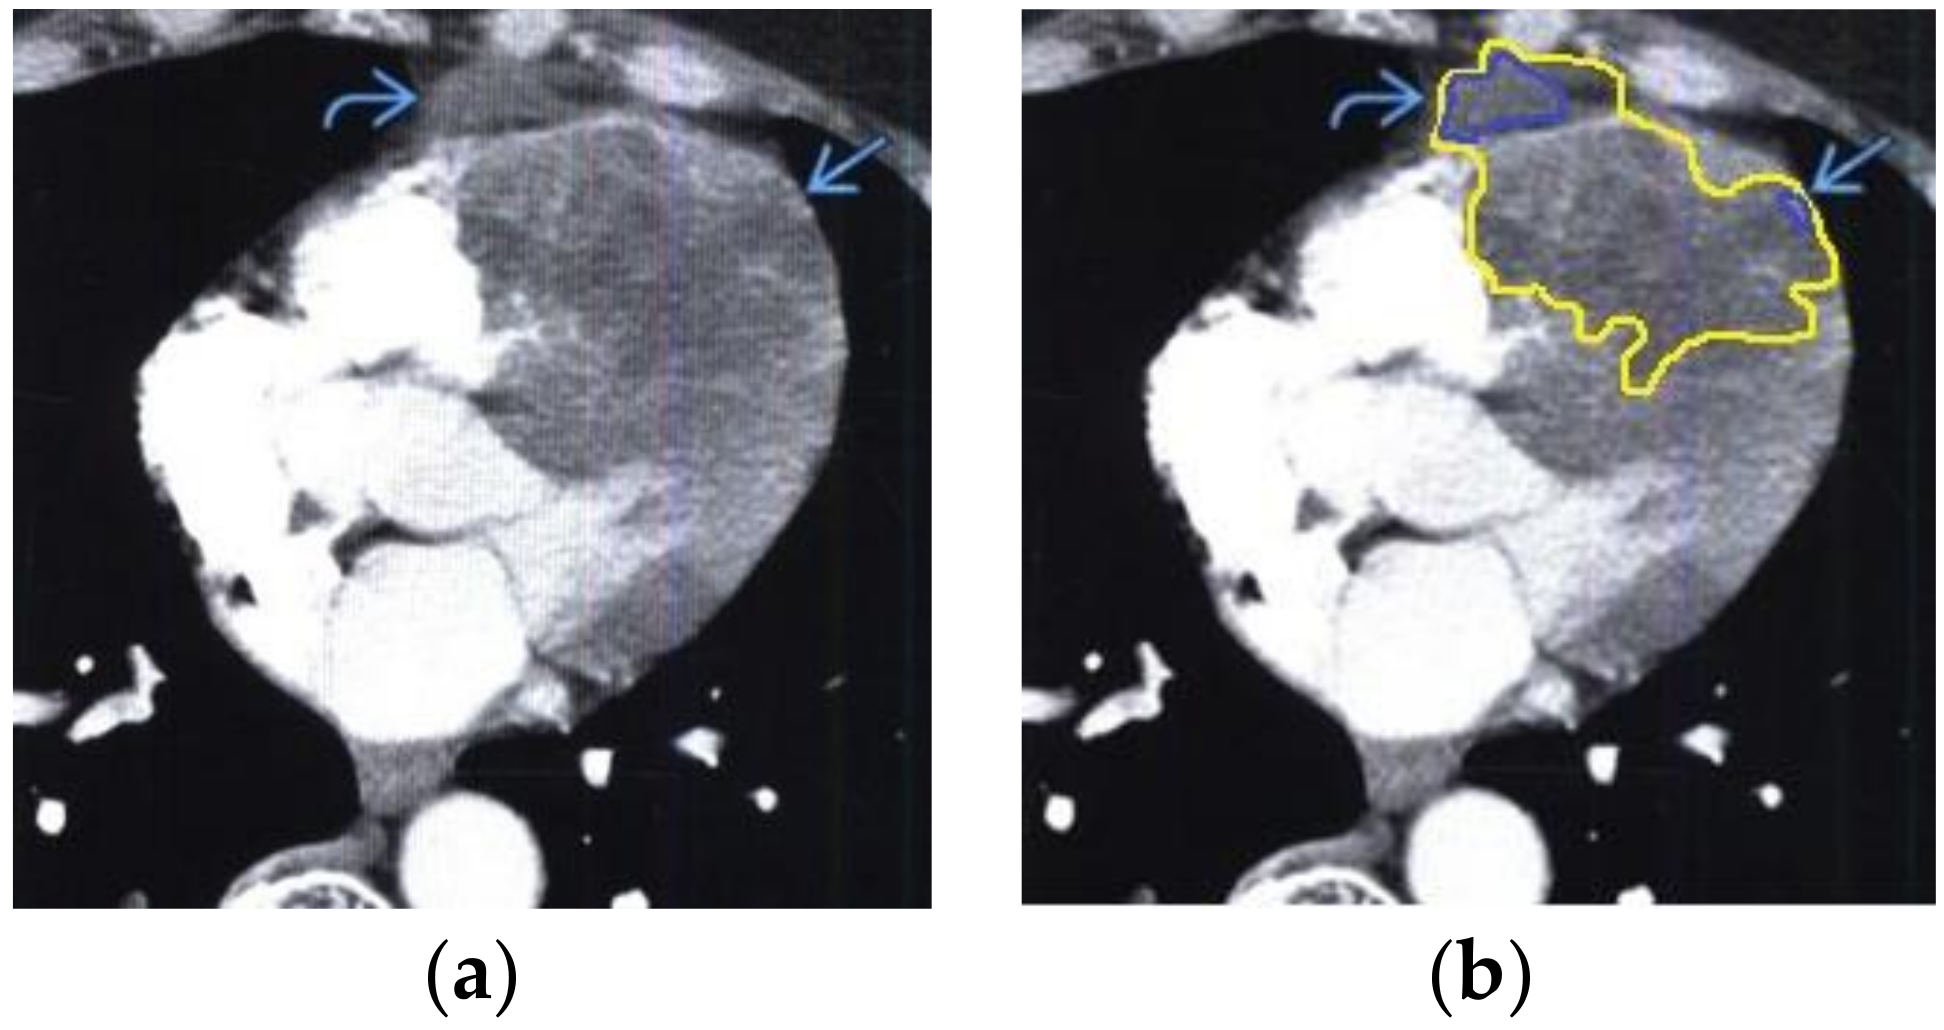

The contour extraction method was used to identify cancerous areas that, after applying the model to eliminate mixed noise, had an increased contrast of volumetric heterogeneous formations in the region of the heart [27]. This method was developed by the authors when analyzing thermal images to assess the condition of the coronary vessels of the myocardium under cardiopulmonary bypass. The contours of the cancerous regions in the examples used for applying the model to eliminate mixed noise (Figure 4, Figure 5, Figure 6, Figure 7, Figure 8 and Figure 9) are highlighted in yellow and they represent the visual boundary of the distribution of volumetric heterogeneous formations.

• For a patient with sarcoma of the heart: during MRI, a volumetric mass was determined in the lateral wall of the right atrium (Figure 7).

Figure 7. Heart MRI: (a) image with white noise and (b) denoised image with contrast enhancement of sarcoma in the right atrium.